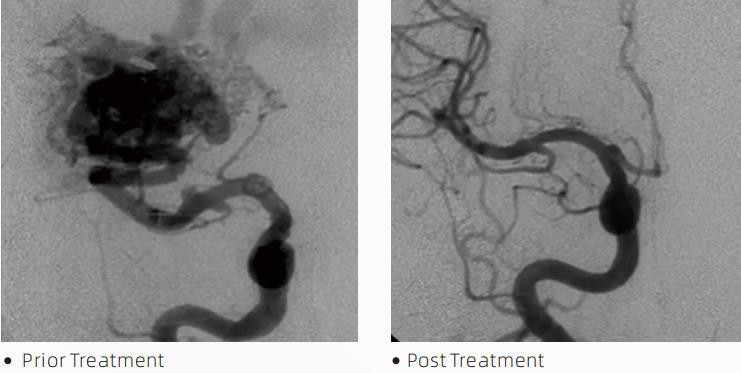

Il-LavaTMLiquid Embolic System hija terapija endovaskulari ta 'intervent għat-trattament ta' malformazzjonijiet ċerebrovaskulari. Malformazzjoni ċerebrovaskulari tirreferi għal grupp ta 'anormalitajiet newrovaskulari beninni jew malinni li jistgħu jwasslu għal emorraġija intrakranjali, infart ċerebrali, iskemija ċerebrali u mard ieħor. Is-sistema ta 'embolizzazzjoni likwida hija apparat mediku amministrat permezz ta' inserzjoni intravaskulari sempliċi, li embolize vini tad-demm ċerebrali anormali billi tinjetta materjal fluwidu speċjali. Il-materjal fluwidu jifforma emboliżmu tat-tessut ikkontrollat fil-vini tad-demm, li jista 'jnaqqas l-impatt ta' malformazzjonijiet ċerebrovaskulari fuq il-pazjenti. Mikrokateter tal-kunsinna kompatibbli mad-DMSO li huwa indikat għall-użu fin-newrovaskulatura jintuża biex jaċċessa s-sit tal-embolizzazzjoni. L-aġent embolic likwidu tal-lava huwa sistema ta 'aġent embolic likwidu mhux adeżiv magħmul minn kopolimeru EVOH (ethylene vinyl alcohol) maħlul f'DMSO (dimethyl sulfoxide), u trab tat-tantalu mikronizzat sospiż biex jipprovdi kuntrast għall-viżwalizzazzjoni taħt fluworoskopija. LavaTMhija disponibbli fi tliet formulazzjonijiet ta' prodotti, LAVA-12, LAVA-18 u LAVA-34. LAVA-12: Rakkomandat meta tmigħ mikro bastimenti distali u permezz ta' feeders żgħar. LAVA-18: Rakkomandat meta l-injezzjonijiet tal-pedicle se jsiru qrib in-nidus; LAVA-34: Rakkomandat għall-embolizzazzjoni ta 'fluss ogħla u komponenti fistulous akbar.